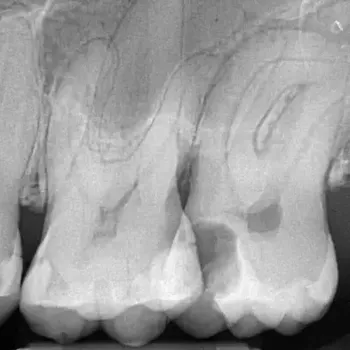

Fall 1: Revisionsbehandlung

Ausgangssituation